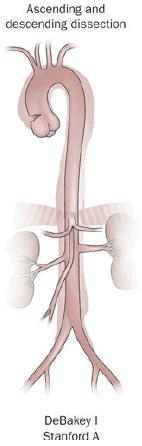

Aortic Dissection

Aortic dissection is caused by shearing force allowing blood leaking through the media of the aortic wall due to an intimal tear.

Aortic dissection occurs in the high-stress zone of the proximal portion of the aorta and is accompanied by medial weakening.

Risk factors of aortic dissection include:

- Hypertension in elderly persons, characterized by vasa vasorum hyaline arteriosclerosis

- Genetic connective tissue abnormalities in younger individuals such as Marfan syndrome or Ehlers-Danlos syndrome, characterized by weak connective tissue and cystic medial degeneration

The media sags as a result of decreased flow.

Weakness of the connective tissue in the media is a characteristic symptom of Marfan syndrome and Ehlers-Danlos syndrome (cystic medial necrosis).

Symptoms of aortic dissection include:

- Intense chest pain

- Chest pain that radiates to the back

Complications of aortic dissection include:

- Death secondary to cardiac tamponade (the most common)

- Rupture with lethal hemorrhage

- Obstruction of branching arteries (such as the coronary or renal arteries)

- End-organ ischemia